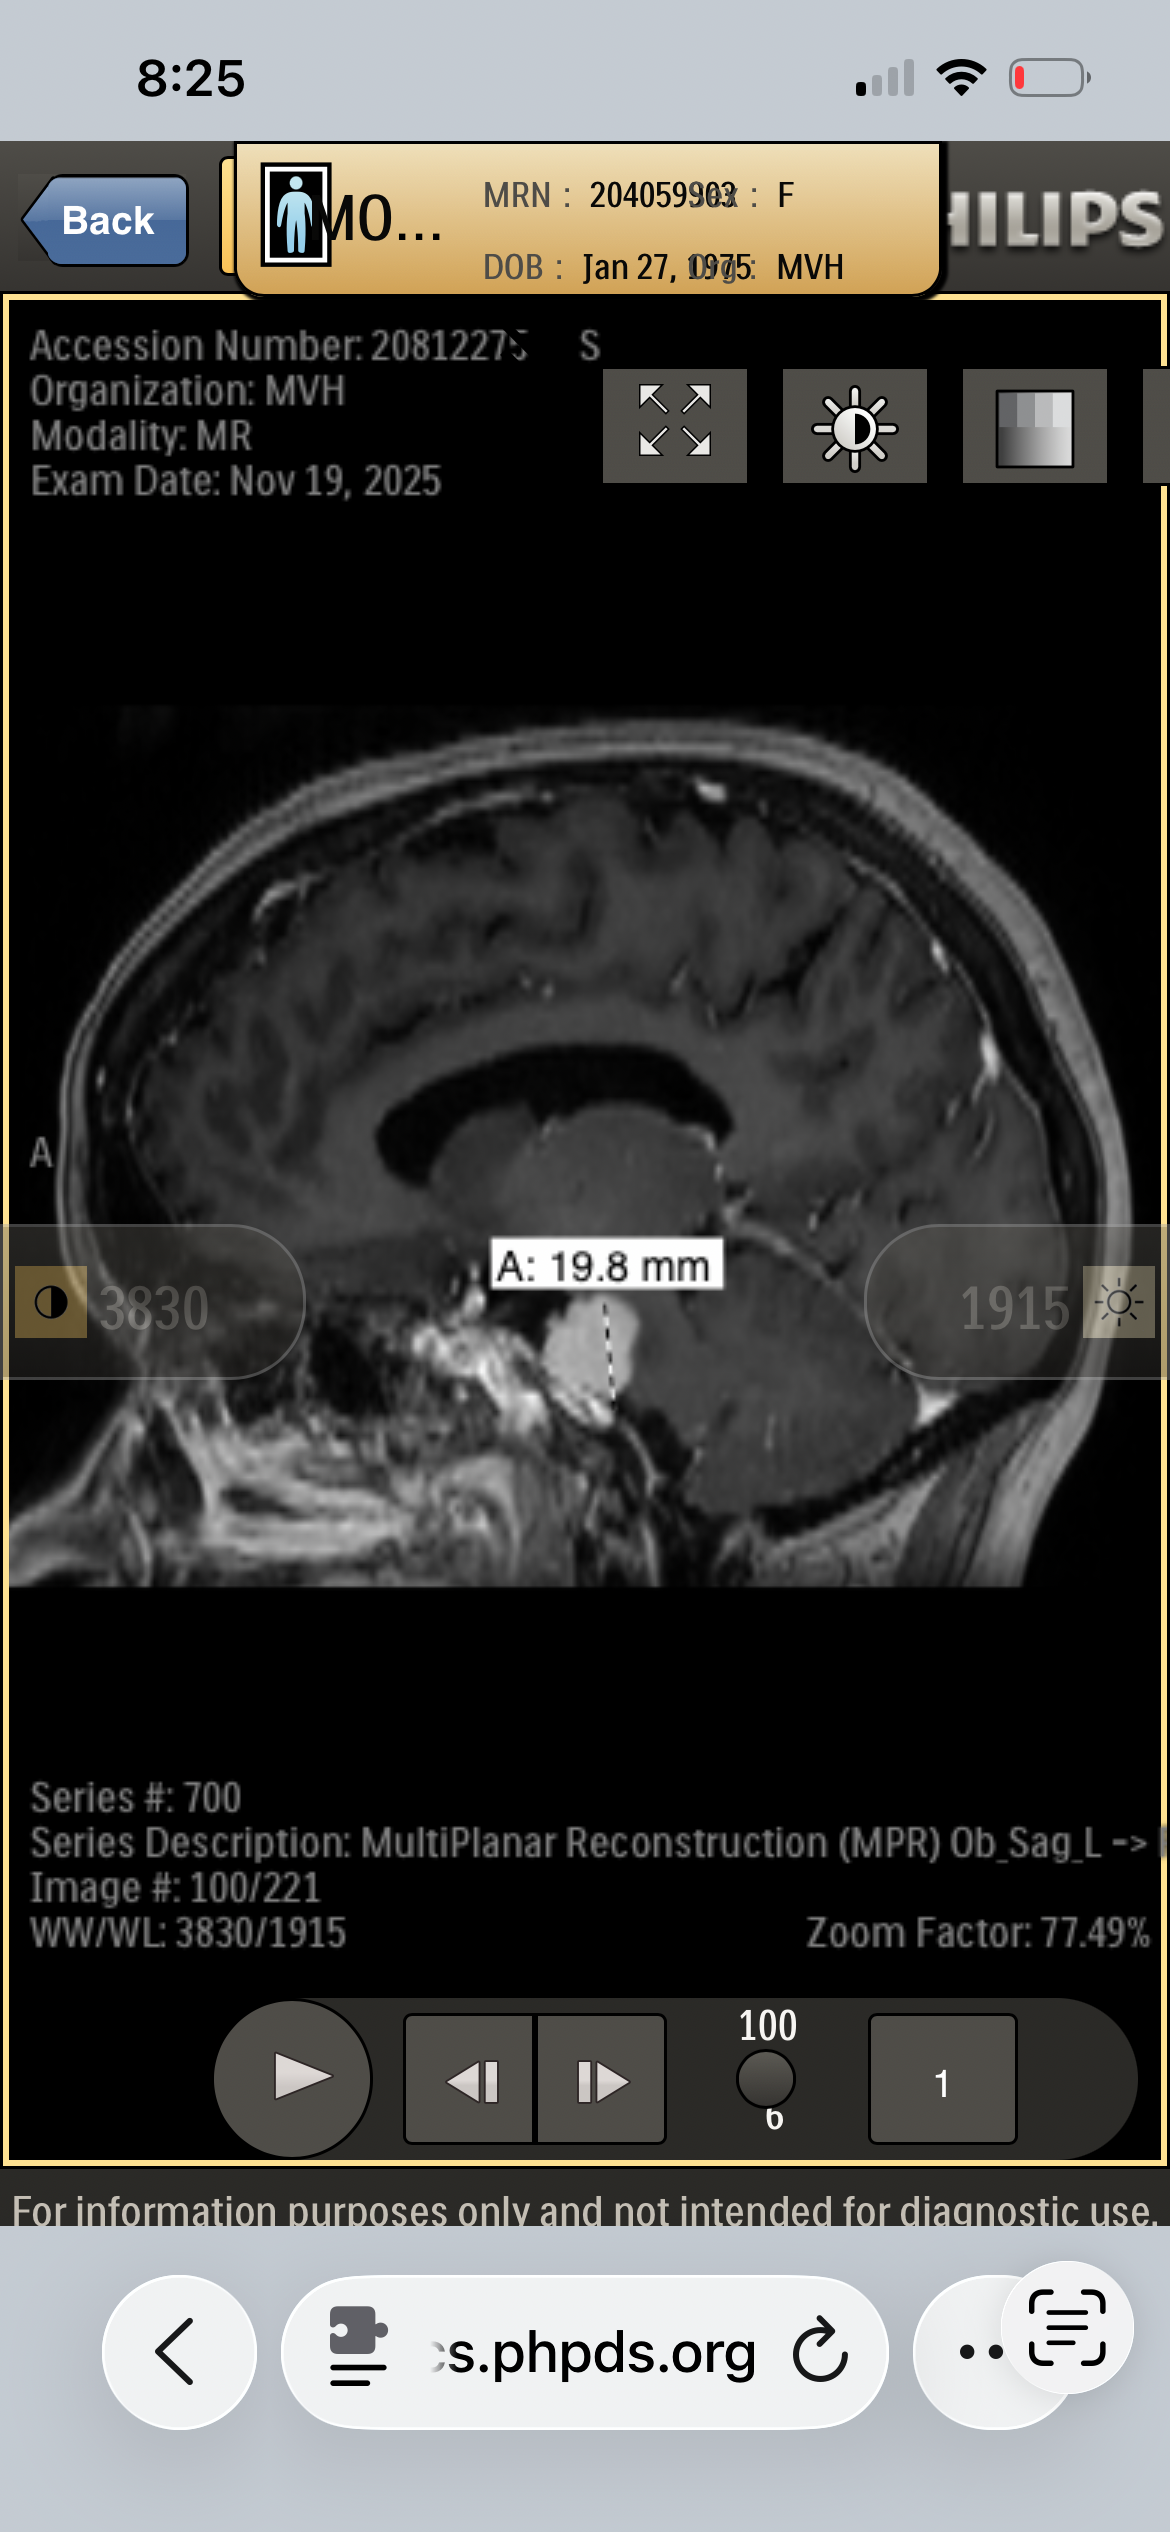

My name is Kory Burge and I'm raising funds for my mom, Angela Montgomery. She is a pediatric cancer survivor, prior pediatric oncology nurse and amazing mom and Mimi. When she was being treated for Stage III B Hodgkin’s Lymphoma in 1991 at the age of 16, they told my grandparents that the long-term concern is developing another cancer due to the harsh chemotherapy and radiation protocol, as well as heart and lung disease. As a parent, what choice do you have? Thirty-five years later, on November 18, 2025 after complaining for over three years to her doctors that something was desperately wrong and being denied an MRI, she convinced the ER doctor to do a CT on her head. They found two large brain tumors, one of which is pressing on and displacing her brain stem. She also has some on her spine, but they’re not sure how many yet. MRI of her entire spine is coming March 6th. This has kept her from working and she has used her retirement down to the penny, and now cannot work, nor support herself through this. Please donate if you can and share this with everyone you know.

The plan is to have the first surgery on March 10th to remove the brain tumor currently displacing her brainstem before it starts causing seizures. It will be 10-12 hours long, then 3 days in ICU and 3 days on the unit. The next will be to remove the one in her frontal lobe.